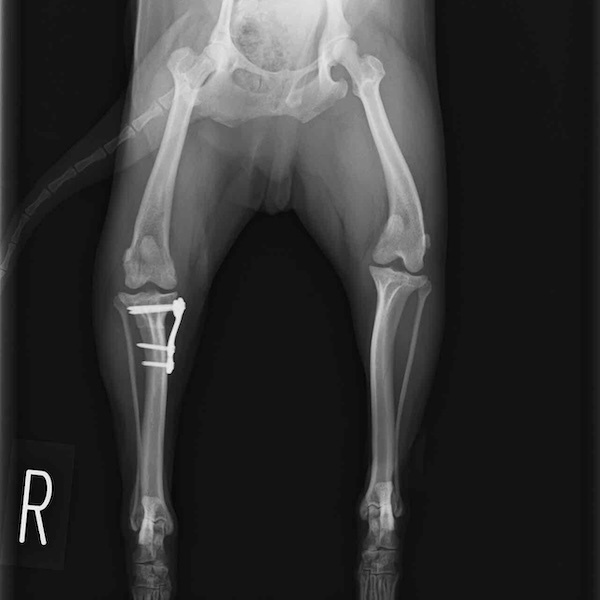

・術後レントゲン

手術前TPA 28.4° が術後TPA 11.7° に矯正されました。

術後1週間で退院。現在は経過観察中です。

術後TPA計測

手術後

当院ではFixinmicroプレートを使用して小型犬のTPLO手術を実施しております。